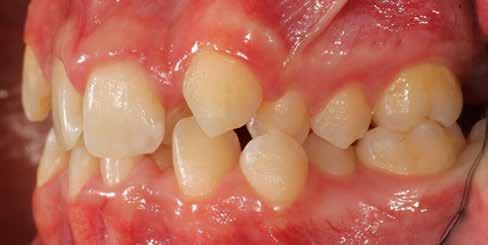

Ebben a cikkben egy 16 éves lánypáciens esetét szeretném bemutatni (1–7. képek)

A Pitts21-es fix készülékes kezelés során a harapásemelőket a felső nagyőrlő fogakra ragasztottuk, hogy a felső molárisok intrúziójával segítsék a harapás zárását (8. kép) Ún. keresztharapásos, majd később normál class 2-es gumihúzással (9–10. képek), továbbá az elülső fogakon alkalmazott ún. Rainbow harapás-záró gumihúzással (11. kép) korrigáltuk a jobb oldali teljes premolárisnyi distal-harapást, valamint az elülső nyitott harapást.